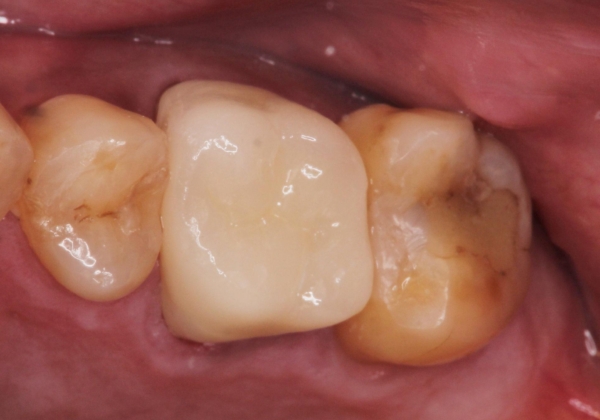

根管治療を行ったのち、症状改善を認めオールセラミッククラウンにて修復治療を行いました。

根管治療にはラバーダムシートをつけて行うことが大切です。マイクロスコープを使用し治療を行いました。治療後、歯の痛みは消失し、とても満足していただきました。

根管治療を行った歯は、再発防止や残された歯質を守るため、クラウンによる補綴治療が必要となります。